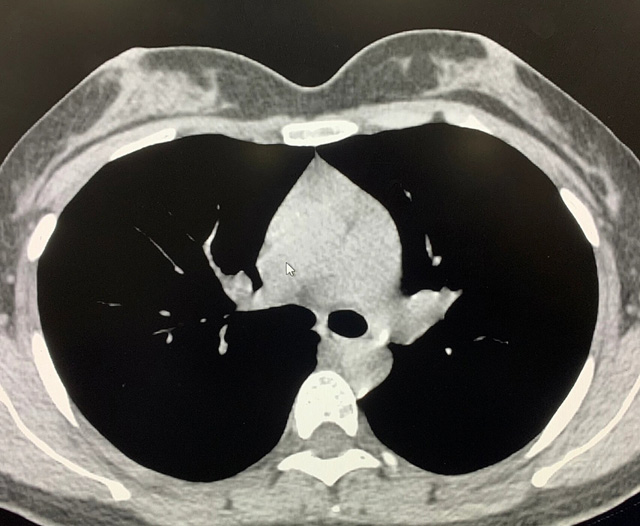

能譜純化技術(shù)的核心是通過物理濾過(如錫濾片)或軟件算法,選擇性濾除低能X射線光子,保留高能光子。在胸部低劑量CT掃描中顯著提升了圖像質(zhì)量與輻射劑量的平衡。

優(yōu)勢輻射劑量顯著降低相較于常規(guī)CT,輻射劑量減少約70%-90%,尤其適合需多次隨訪的高危人群(如肺癌篩查),降低輻射相關(guān)癌癥風險早期肺癌篩查效果明確可清晰檢測毫米級肺結(jié)節(jié),顯著提高早期肺癌檢出率,降低死亡率。檢查快捷且普及性高單次掃描僅需數(shù)秒,無需對比劑,設(shè)備廣泛配置于基層醫(yī)院,便于大規(guī)模篩查。長期成本效益顯著雖單次費用與常規(guī)CT相近,但早期干預(yù)可大幅降低晚期治療費用及社會醫(yī)療負擔。技術(shù)優(yōu)化提升圖像質(zhì)量迭代重建算法(如ASIR、MBIR)在降低劑量同時減少噪聲,平衡影像質(zhì)量與安全性。